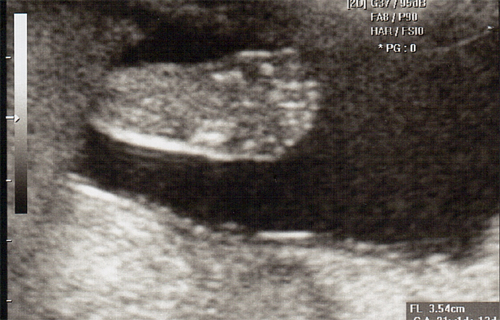

강아 ^^ 21주 강이의 정밀 초음파를 봤어 일반 초음파 보다는 더 정밀하게 나오더라구 엄청 커버린 강이가 한눈에 보이지 않을정도로 이제는 초음파 기계가 작아 보이더라..

강이 얼굴을 딱~ 보는순간.. 심장이 멈추고 코를 보는순가 다시 심장이 뛰기 시작했어 딱.. 아빠 코를 닮았더라 ^^:.. 이쁜자식...

다음에 가면 입체 초음파를 볼꺼야 더더욱 아빠를 닮은 강이를 볼수 있겠지 기대가 된다